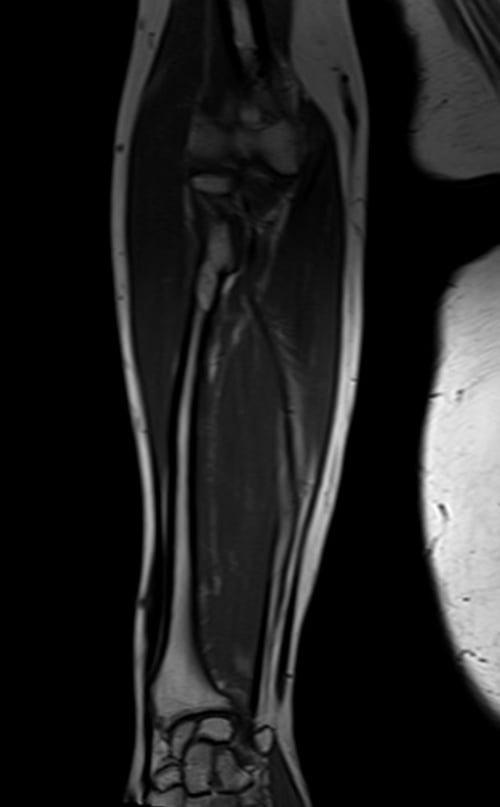

mri fore arm coronal t1 image 3 - MRI